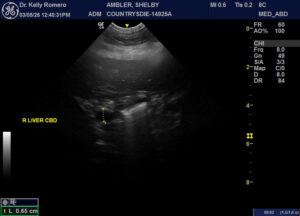

7 year 9 month old FS Chow with lethargy, vomiting and intermittently dribbling blood tinged urine. CBC WNL. Chem – ALT 773, ALP 389, GGT 31, T bili 0.5. Looks like choleliths in biliary tree, but focal region. No reported fever. Started Ursodiol, Denamarin, and antibiotics for cholangiohepatitis (Clavamox and metrondizadole). Urinary bladder looked unremarkable. There was a hyperechoic nodule in the otherwise normal left adrenal gland.

Rocks in the cbd… may need sx if she doesn’t pop them through the d-pap. Always scan right before cutting.to ensure the song remains the same 🙂

Hi Eric, thank you for taking a look! When I go back through, I can see where some of these hyperechoic choleliths could actually be in the gall bladder instead of outside of it – is there an artifactual phenomenon that causes them to look more like they are outside of the lumen at least in some views or do you think it is a combination of choleliths in the GB and the nearby tree?

Do you think medical treatment is an option in this case while monitoring LE (ursodiol, antibiotics) or best to refer for surgery? CBC looks empty to me, but distended – did I miss a stone in there?